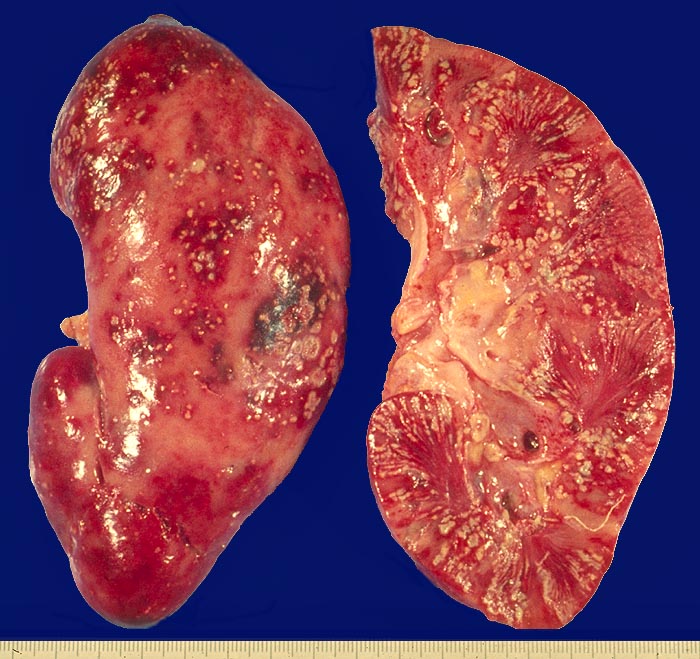

AP/ Akute Pyelonephritis

Akute Pyelonephritis

Makroskopisch sind die Nieren vergrössert. Die Oberfläche ist oft von Gruppen stecknadelkopfgrosser gelblicher Eiterherde mit rotem Randsaum übersät. Auf der Schnittfläche sind streifenförmige Eiterherde mit rotem Randsaum, gelegentlich Abszesse, akute Papillennekrosen (> 1759) (> 1786), eine Pyonephrose (eitergefülltes Nierenbecken) (> 1763) oder eine subpelvine Phlegmone (> 1760) nachweisbar. Beim akuten Schub einer chronischen Pyelonephritis sind zusätzlich Narben vorhanden. Pyelonephritische Herde sind histologisch gekennzeichnet durch eine zentrale eitrige Einschmelzung mit Gewebsdestruktion. Das umgebene Gewebe wird infiltriert von neutrophilen Granulozyten untermischt mit einzelnen Lymphozyten, Plasmazellen und Histiozyten. Der rote Randsaum wird verursacht durch die entzündliche Gefässhyperämie.

• Streifenförmige Entzündungsherde erstrecken sich vom Mark bis in die Rinde.

• Hyperämie des angrenzenden Parenchyms.

• Destruktion der Nierentubuli durch neutrophile Granulozyten innerhalb der Herde.

• Sammelrohre angefüllt mit neutrophilen Granulozyten.